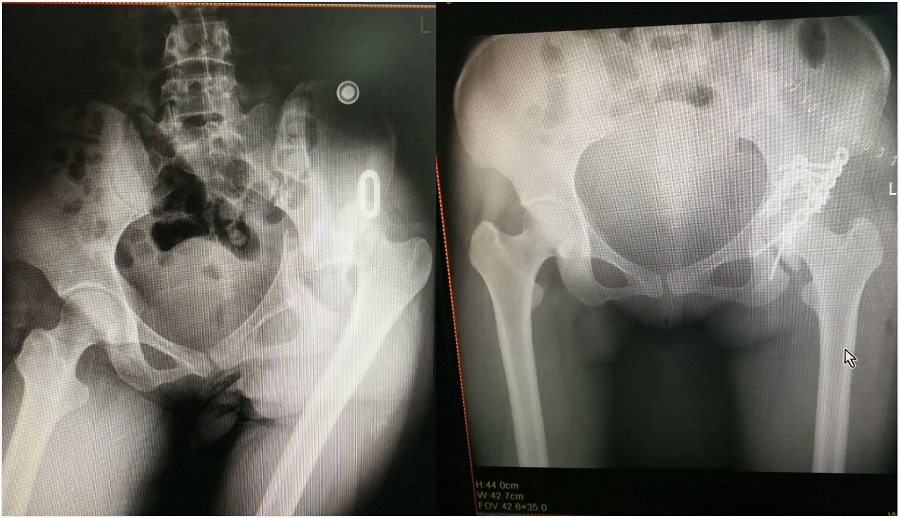

骨盆骨折一般多由于高能量外傷所致,受傷時(shí)所受到的暴力巨大,如高處墜落傷、重物的砸傷、嚴(yán)重的交通事故等?;颊咄跖考词且蜍嚨湆?dǎo)致骨盆髖臼關(guān)節(jié)面骨折伴髖關(guān)節(jié)脫位、聯(lián)合前后柱粉碎性骨折入住我院骨一科,考慮到該患者骨折面積大,且伴隨脫位、其他部位粉碎性骨折,極有可能損傷坐骨神經(jīng)機(jī)能。經(jīng)過對(duì)患者的檢查、病情分析,如不手術(shù)治療,患者將終生臥床,失去下地行走的機(jī)會(huì),給家庭帶來(lái)巨大的災(zāi)難。骨一科醫(yī)生當(dāng)即表示,要舉全科之力救治這例危重的骨折病人!通過楊連根主任、朱迪喜主任、徐建華主任、栗慶東主任縝密的手術(shù)評(píng)估,完善了術(shù)前檢查,制定了將風(fēng)險(xiǎn)降到最低的手術(shù)方案。

12月17日上午,在北京積水潭醫(yī)院創(chuàng)傷骨科劉亞波教授的大力支持下,我院楊連根主任、徐建華副主任為患者成功進(jìn)行固定、復(fù)位。目前患者恢復(fù)良好,無(wú)內(nèi)臟、神經(jīng)損傷等并發(fā)癥。